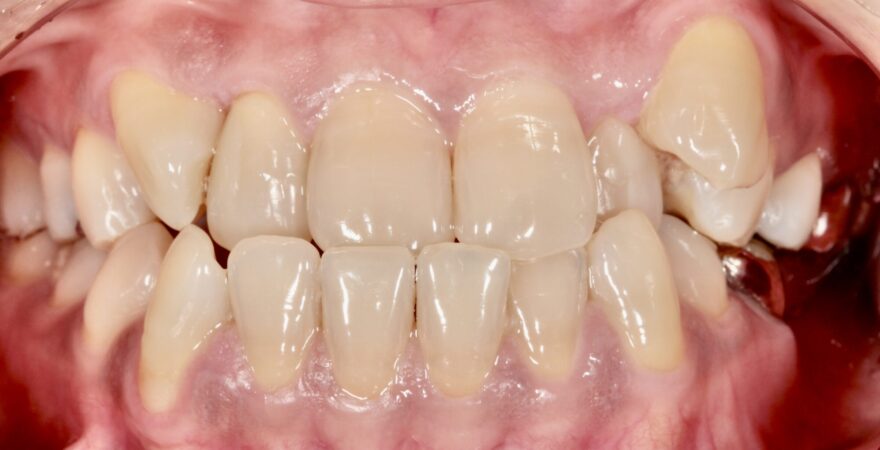

初診時の口腔内写真

左下の奥歯が崩壊しています。

右下の奥歯を失い、噛み合わせが歪んでいることが分かります。

右上の八重歯が気になります。